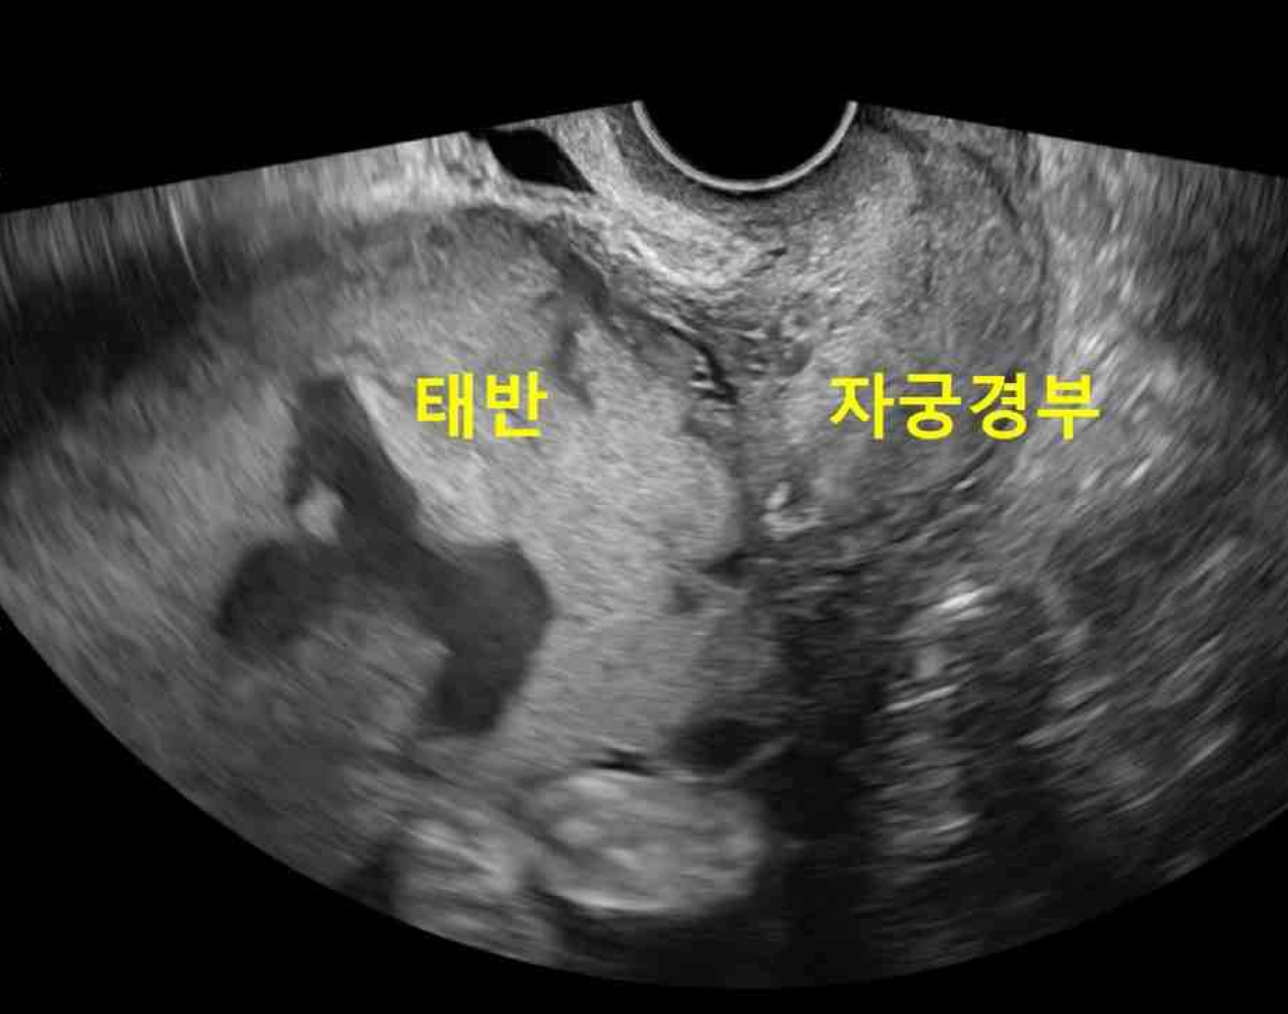

임신 33주인 36세 다분만부가 아랫배 불편감으로 병원에 왔다. 이전에 제왕절개로 분만하였다. 혈압 110/70 mmHg, 맥박 90회/분, 호흡 18회/분, 체온 36.7℃이다. 골반검사에서 자궁경부를 통해 나오는 출혈은 보이지 않는다. 초음파검사 사진과 전자태아심박동-자궁수축감시검사 결과이다. 혈액검사 결과는 다음과 같다. 처치는?

US: Placenta previa

• 현재 산모와 태아는 초음파상 placenta previa외에 특이사항이 확인되지 않으므로 조속한 분만이 필요하지 않다고 판단된다. 따라서 태아 폐성숙을 촉진하기 위한 corticosteroid 투여 시간을 확보하기 위해 자궁수축억제제(tocolytic)를 사용할 수 있다.

• 제왕절개: 본 증례의 산모의 경우 제왕절개술 과거력과 placenta previa가 확인되므로 추후 분만 시 제왕절개술을 고려해야 함은 맞다. 하지만, 현재 태아와 산모의 상태에 특별한 이상이 확인되지 않으므로 조속한 분만을 고려할 필요는 없다. 현재 34주 미만의 조기진통이므로 폐성숙 촉진을 위한 스테로이드 투여 및 이를 위한 자궁수축억제제 사용이 고려되어야 한다.